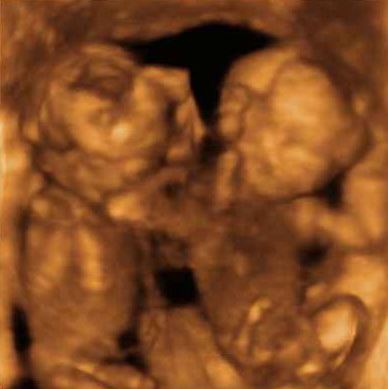

İkiz Gebelik Ultrason Görüntüleri